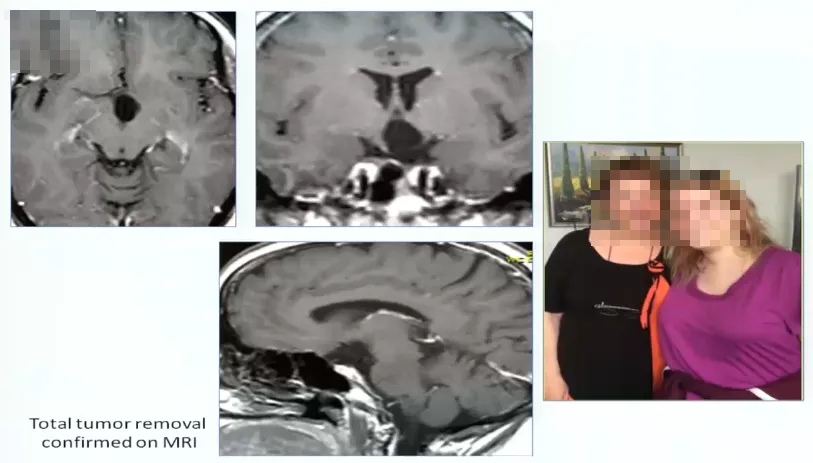

手术病例1:

24岁女性、闭经,胶质瘤主要累及下丘脑

术中情况:患者视路、视交叉肿胀非常明显。接下来显示通过翼点入路视角处理丘脑胶质瘤的情况。直接切开视交叉部位,然后打开中板,松解嗅神经,否则会因牵拉额叶造成嗅神经嗅丝断裂。三室完全被肿瘤充满,好消息是肿瘤和脑室壁有很好的界限。瘤脑界面清楚,肿瘤大部分清除,先做活检。做完活检,然后kusa进行肿瘤大部分减容,一定要分离的时候牵拉轻柔,不要把肿瘤夹得过碎,以方便大块切除。1.4mm检查周围穿支保留及是否有肿瘤残留,一定要仔细检查瘤仓的各个角落,确保没有残留。

术后情况:肿瘤全切,患者情况良好。